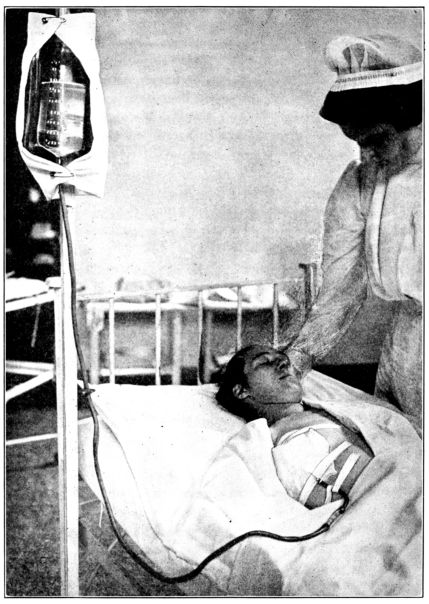

| 49. | Method of giving infusion | 202 |